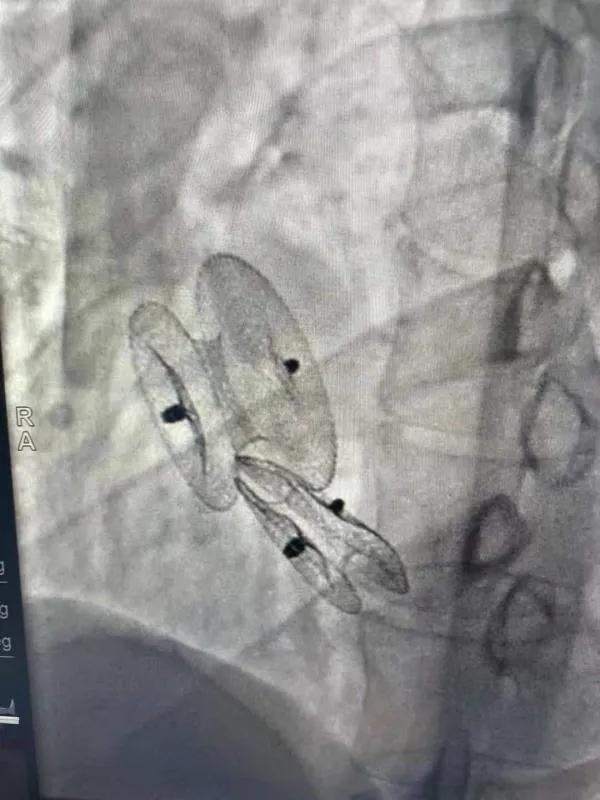

先天性心臟病房間隔缺損呈多孔型怎么辦?患者并非只能選擇開(kāi)胸手術(shù)。近日,西安國(guó)際醫(yī)學(xué)中心醫(yī)院心臟病醫(yī)院成功開(kāi)展一例雙孔房間隔缺損雙傘介入封堵術(shù)。

房間隔缺損是先天性心臟病的一種,介入手術(shù)相較于傳統(tǒng)的外科手術(shù)損傷小,風(fēng)險(xiǎn)相對(duì)較低,術(shù)后恢復(fù)快。一般的房間隔缺損多呈單孔,封堵難度較小,而雙孔房間隔的封堵難度大大增加,至今僅有國(guó)內(nèi)頂尖的封堵專家成功完成了數(shù)例而已。

患者是位27歲的年輕女性,經(jīng)常感到心慌,心臟超聲發(fā)現(xiàn)房間隔缺損,并且房間隔缺損呈雙孔型,大的約14mm,小的約9mm,兩個(gè)缺損間相隔較遠(yuǎn),介入封堵難度非常大。

在詳細(xì)了解患者病情,仔細(xì)閱讀患者影像資料后,曾廣偉主任已經(jīng)有了清晰的手術(shù)策略。在精心的準(zhǔn)備和團(tuán)隊(duì)的配合下,曾主任順利的利用兩個(gè)封堵器對(duì)房缺進(jìn)行了封堵。